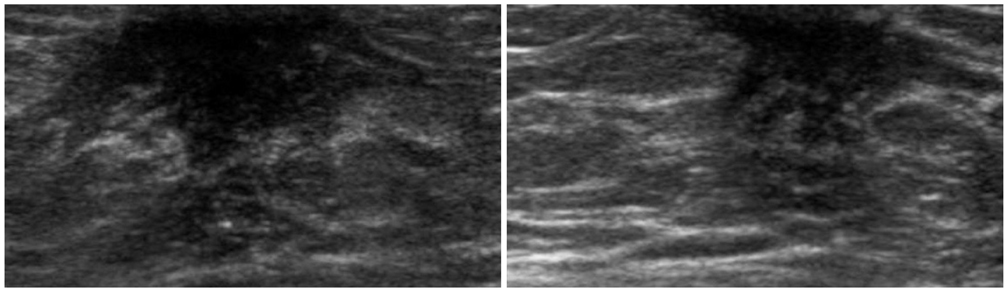

- The purpose of this study is to review various breast diseases in children and adolescents and to illustrate the sonographic findings. We reviewed the cases at our institution in order to identify breast disease in children and adolescent patients who underwent sonography and mammography. Breast disease in children and adolescents included developmental disturbance, infection, benign tumors and inherent defects. In contrast to adults, the radiologic findings of malignant breast conditions in pediatric populations have rarely been reported; however, we show ductal carcinoma in situ with juvenile fibroadenoma and rhabdomyosarcoma. During childhood and adolescence, the recognition and correct identification of physiologic breast development and specific lesions in breast entities on radiologic findings is most helpful in identifying and characterizing abnormalities and in guiding further investigation.